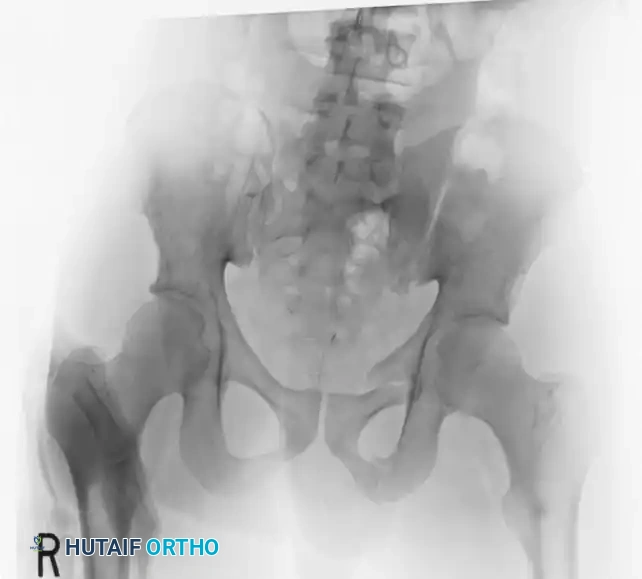

Preoperative Evaluation:

The preoperative AP, inlet, and outlet views demonstrate severe pubic diastasis, bilateral pubic rami fractures, and gross widening/displacement of the posterior SI joints.

FIGURE 56-45: Young and Burgess anteroposterior type III (AP III) pelvic ring injury with pubic diastasis and bilateral pubic rami fractures. A-C, Preoperative anteroposterior, inlet, and outlet views, respectively. D, Preoperative CT scan.